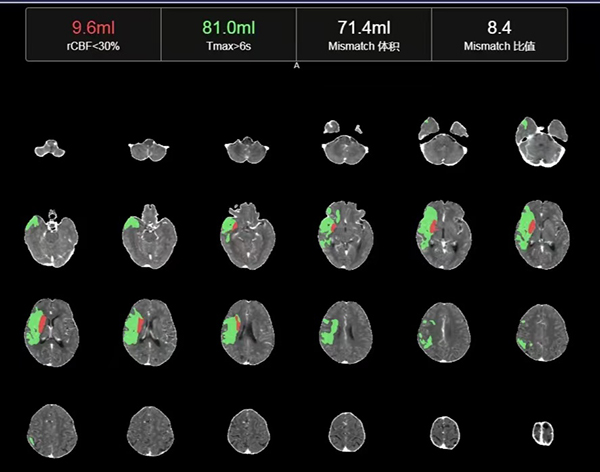

CTP检查结果提示,姬阿姨颅内核心梗死体积约9.6ml(红色区域),但低灌注区域体积高达81ml(绿色区域)(图2),低灌注区域越大,代表可挽救的脑神经细胞越多,手术开通的价值越大,可见患者颅内低灌注区域远远大于核心梗死区域,颅内动脉取栓术手术指征进一步明确。在与患者家属积极沟通,征得家属同意后,王建峰主任团队在国家级高级卒中中心李健主任的指导下,急诊进行了全脑血管造影术+颅内动脉取栓术,术中证实右侧大脑中动脉起始段闭塞(图3),并急诊进行了右侧大脑中动脉取栓术,术中抽拉出一块暗红色血栓,术后可见右侧大脑中动脉血流通畅(图4)。术后1周,在神经内科一病区医护人员的精心照料下,姬阿姨完全康复,说话言语清晰,对答切题流畅,四肢肌力活动恢复正常,现已康复出院。

图2